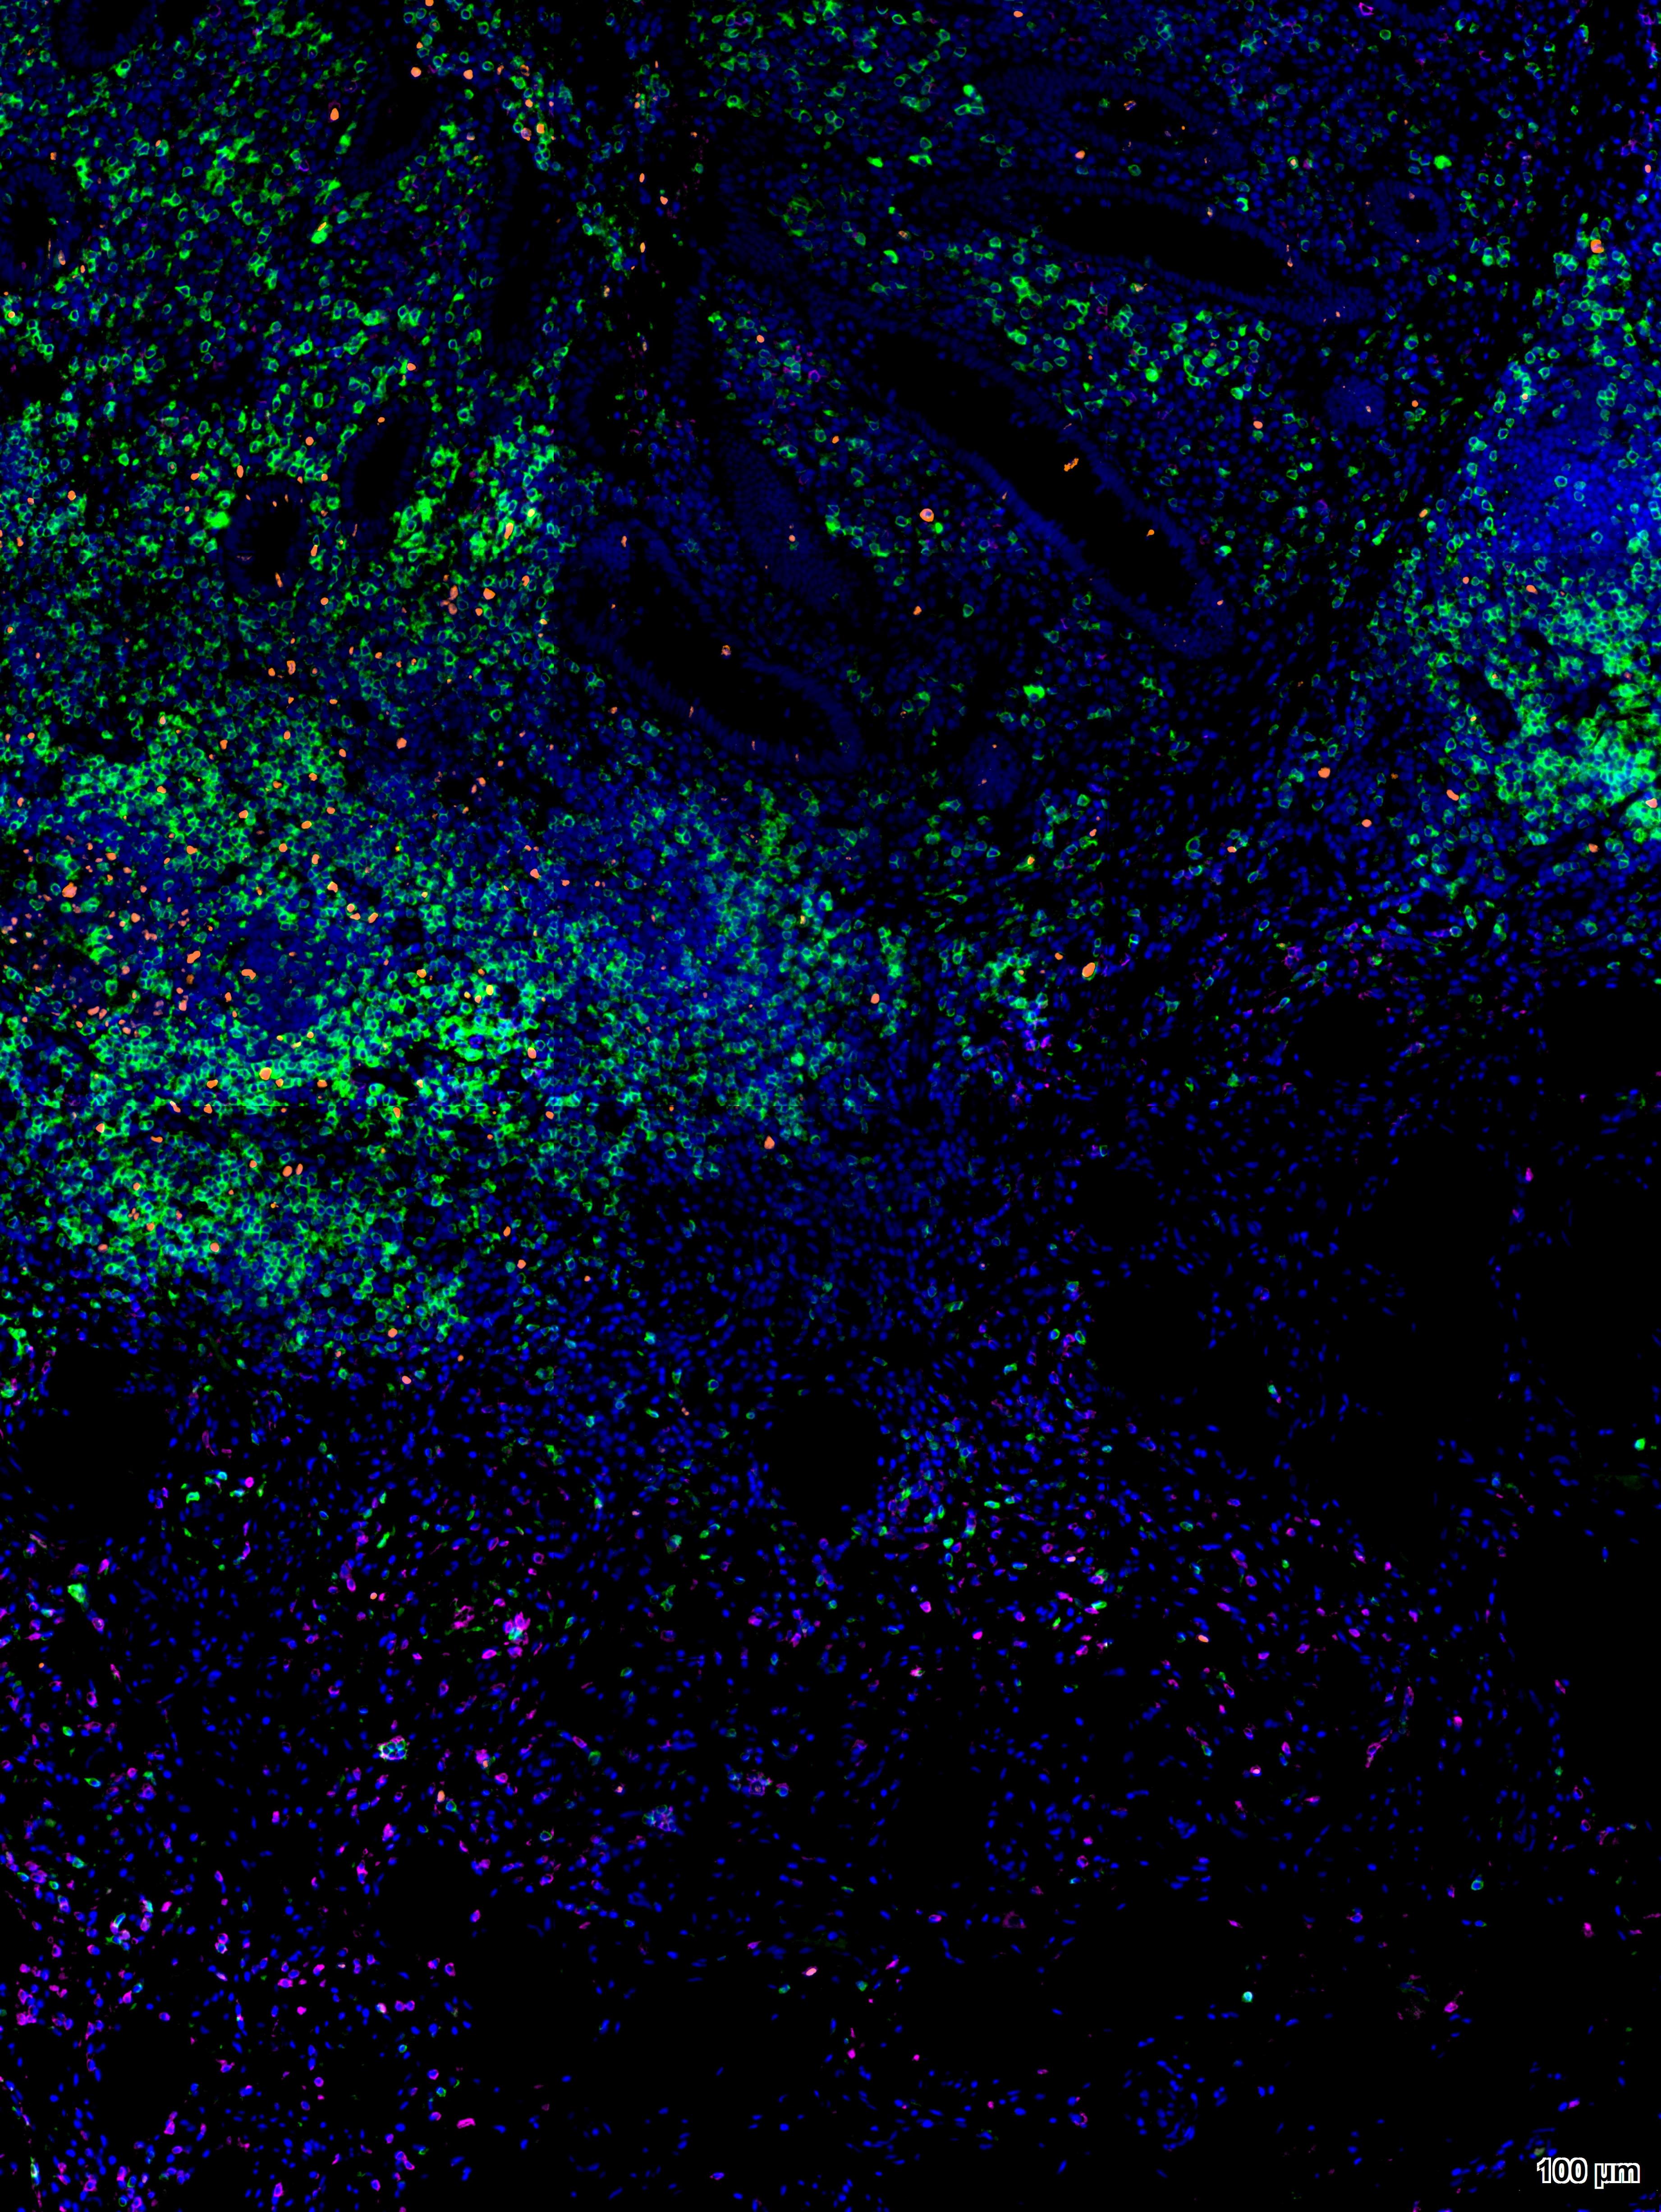

酪酰胺信号放大(TSA, Tyramide signal amplification)技术是一类利用辣根过氧化酶(HRP)对靶蛋白进行原位标记的酶学检测方法。其原理是利用酪胺(Tyramide)的过氧化物酶反应,酪胺荧光素底物在HRP和H202的作用下被活化,活化的荧光底物能与目标蛋白上的酪氨酸等残基共价结合,导致在抗原-抗体结合位点大量沉积荧光素,实现信号放大。通过热修复或者抗体洗脱液洗去前一轮非共价结合的抗体,而荧光素稳定结合在蛋白上,进行下一轮染色。直至所有抗体孵育结束,进行核染色,封片,扫描。

由于每次体系中都只有单一抗体孵育,因此无需担心抗体的交叉反应及一抗二抗种属匹配问题,摆脱了传统免疫荧光实验条件对抗体种属来源的限制和束缚。此试剂盒中的荧光染料可以单独或组合使用,能够实现单标、双标、三标以及更多重荧光放大/多重同源抗体荧光标记等功能。